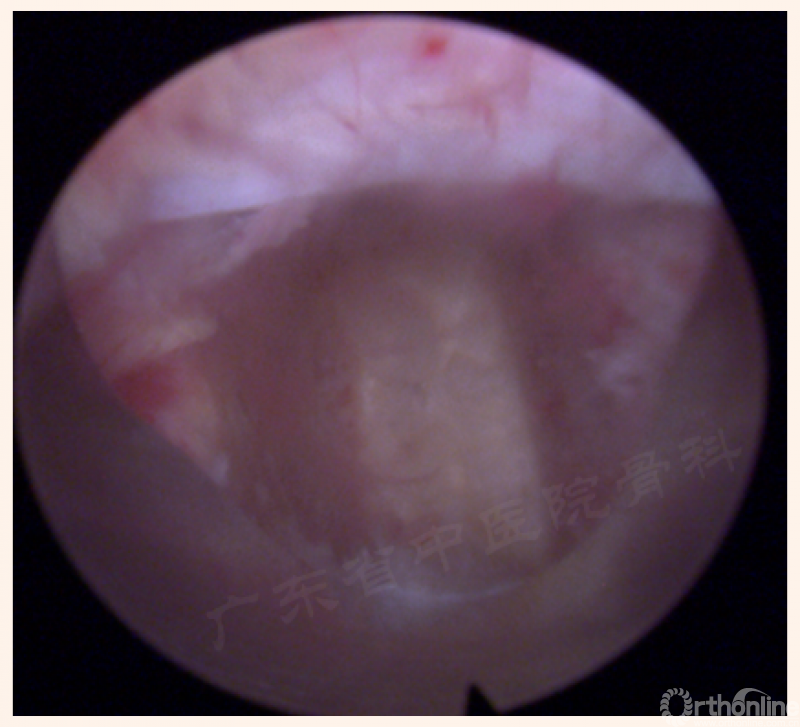

1. 椎间盘显露及开口

(21、22、23、24动图待完善)

2. 后缘处理—颈椎?

3. 进入间隙

关键点-空间

远端

外侧